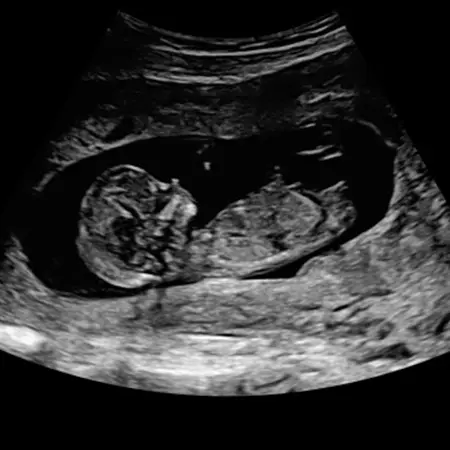

Image

Γ' τρίμηνο